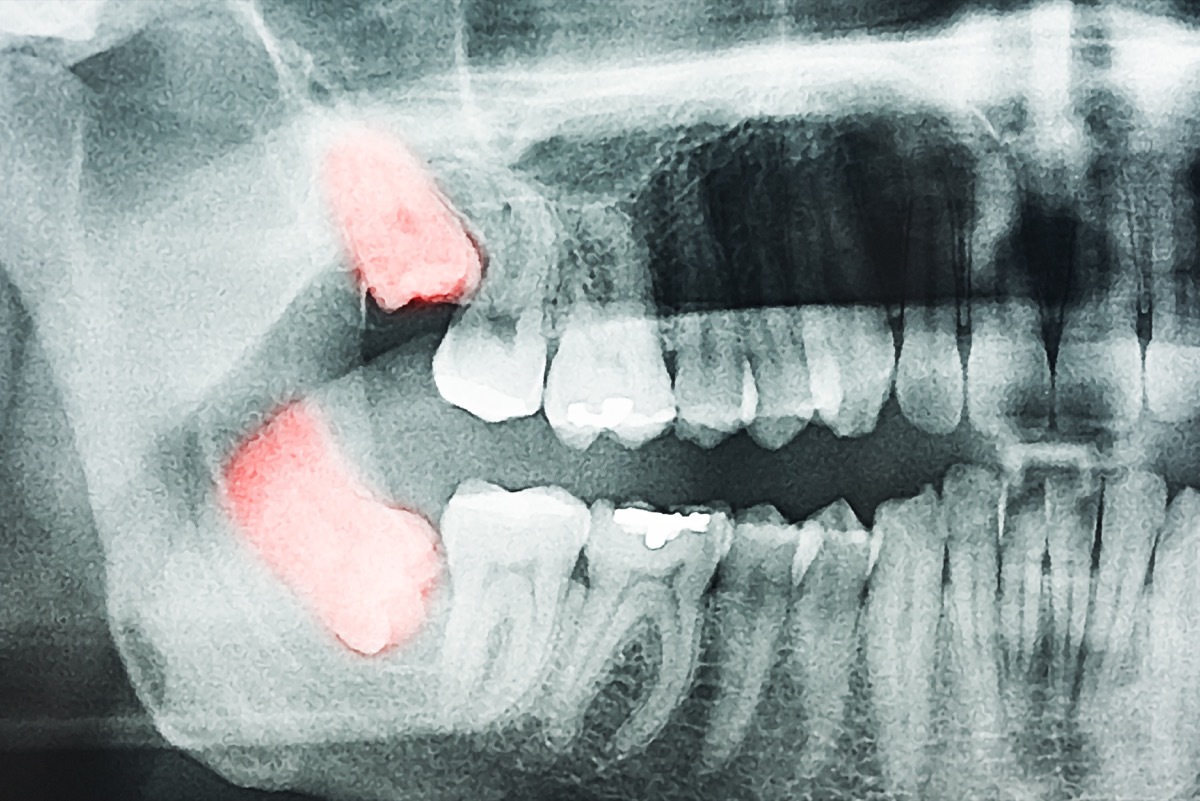

Wenn Ihre Zahnschmerzen mit dem Druck verbunden sind, kann dies darauf hindeuten, dass Ihre Weisheitszähne Ihnen Ärger geben. Laut einer Studie vonDr. Jay W. Friedman, DDS, MPH, 10 Millionen Weisheitszähne werden jedes Jahr in den Vereinigten Staaten extrahiert. Ihre Weisheitszähne wachsen den größten Teil ihres Wachstums und ändern sich, wenn Sie 16 bis 23 Jahre alt sind.

Wenn sie in den in diesen Jahren normal gewachsen schienen, hat sich der Zahnarzt zu dieser Zeit möglicherweise entschieden, sie in der Zeit zu bleiben. Wenn Sie jedoch älter werden, können sie immer noch anfangen, Ihre anderen Zähne zu stellen. Wenn Ihre Weisheitszähne in einem Winkel in einem Winkel wuchsen, sind sie anfälliger für Infektionen oder Zahnverzögerungen, die andere Probleme in Ihrem Mund verursachen können, wenn sie nicht herausgenommen werden.

Der rx: Sehen Sie sich Ihren Zahnarzt an, damit er oder sie X-Strahlen aus Ihrem Mund nehmen und sehen, was mit Ihren Weisheitszähnen los ist. Wenn sie anfangen, Ihre anderen Zähne zu stellen, oder nicht gesund auszusehen, müssen Sie möglicherweise für Ihren Zahnschmerz und den Druck entfernen, um endlich zu verschwinden.